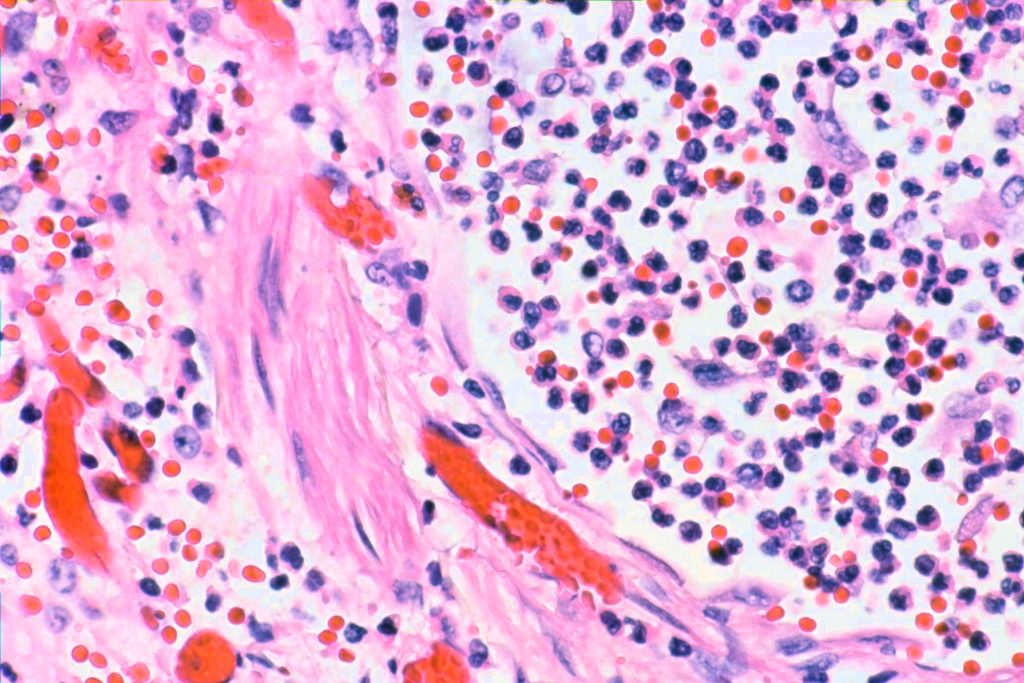

2. There should be foci of fibroblast proliferation, called, not surprisingly “fibroblast foci” in the literature. They are little lumps of fibroblasts, with the lumps usually flat on one side and rounded on the other.

In this case there was a brochopneumonia as well. The decedent had been under terminal sedation for a few days:

And an associated acute bronchitis: